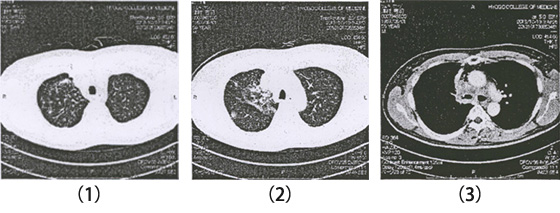

漢方治療前

漢方治療前、抗がん剤で腫瘍がやや縮小。その後、全身状態が悪く抗がん剤中止。

漢方治療1年後、原発巣が消失されて、肝転移も消失された。